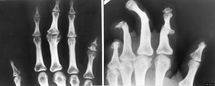

Mains

Arthrose, Polyarthrite rhumatoïde